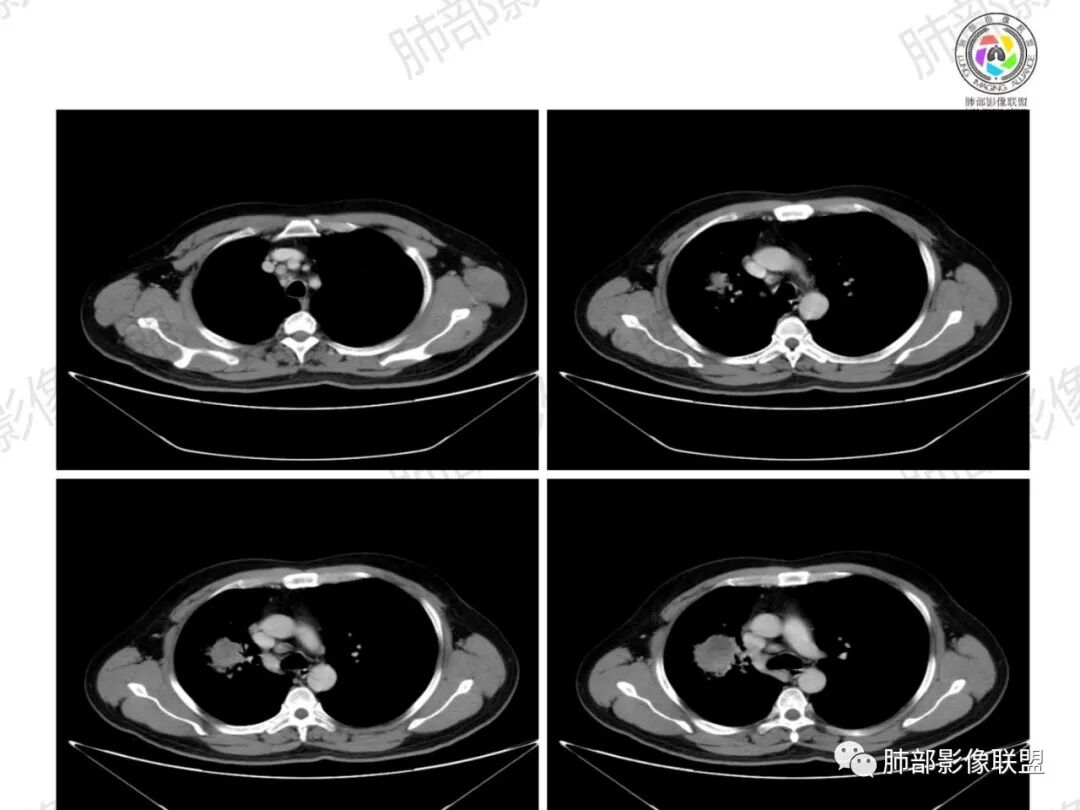

纵隔淋巴结肿大并不明显,就这一个肿大较明显,但仍呈椭圆形,中心少许坏死。

1、坏死区内寸草不生;2、病灶环形强化;3、远端树芽和结节;4、远端不是阻塞性炎症,而是树芽和结节,右肺上叶前后段都有,后段为主,而堵塞的支气管应该是前段;这些树芽的位置不是堵塞支气管的责任区;5、支气管不是突然截断堵塞,而是逐渐狭窄;6、纵隔淋巴结是椭圆形增大,内有坏死,不是肿瘤的圆形饱满;7、支气管周围粘液样坏死,符合仙人掌结核改变;

8、右侧胸廓塌陷。

4、纵隔淋巴结肿大:这个病例的淋巴结肿大,不是圆形饱满,而是椭圆形,中间坏死。